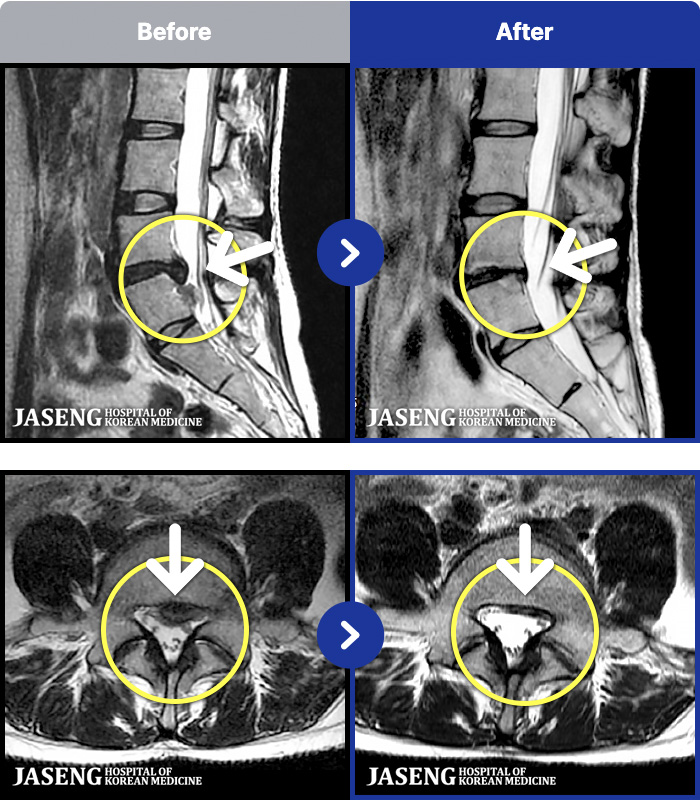

1,257 MRI ũ ʸ Ȯϼ.